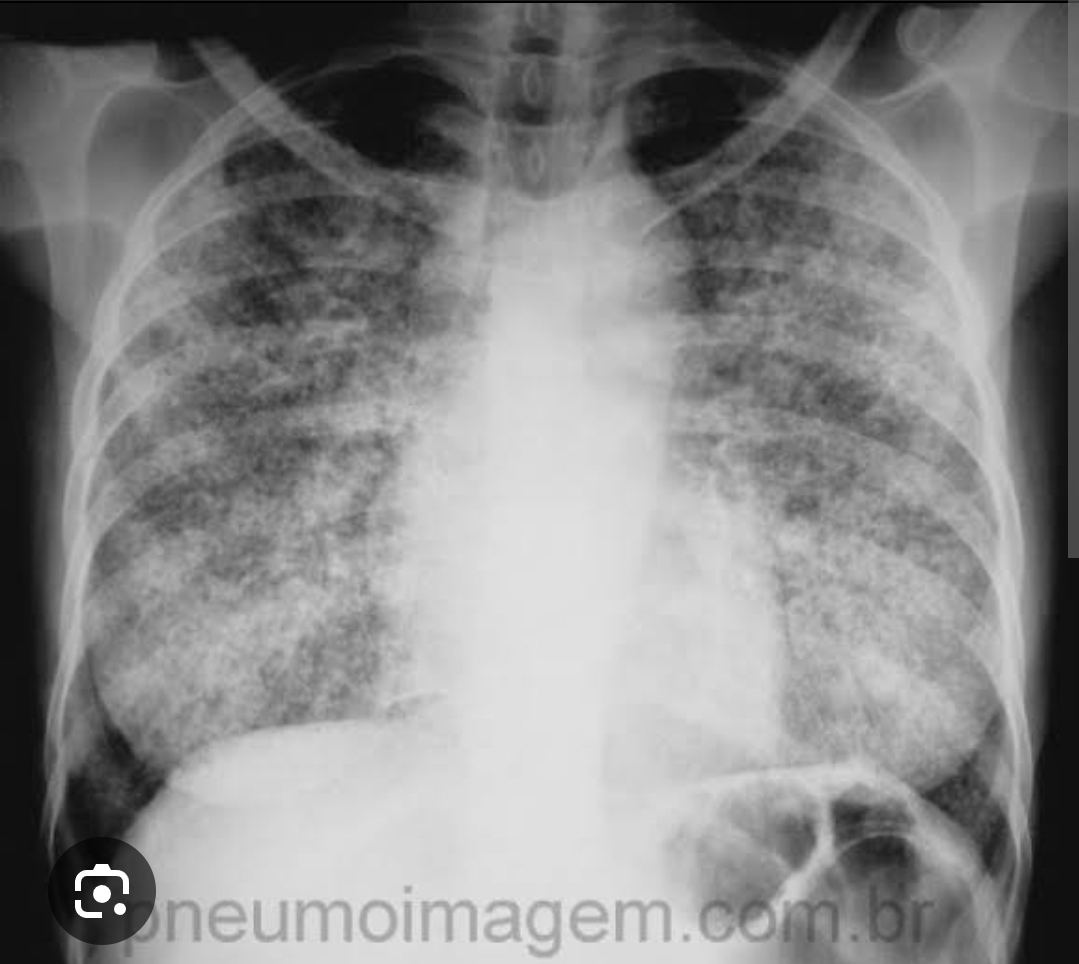

Q

Espessamento do espaço intersticial, seja por congestão pulmonar ou fibrose .

Formação de redes reticulares no pulmão do centro para periferia, devido aos espessamento dos intersticio.